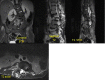

Disseminated tuberculosis is characterised by concurrent tubercular involvement of two or more non-contiguous organs. It is an unusual presentation of tuberculosis, especially in the absence of immunodeficiency. We describe a young, immunocompetent patient who presented with fever, cough, headache, diplopia and paraparesis. On examination, the patient had positive Kernig's sign, right third cranial nerve palsy and bilateral sixth cranial nerve palsy, bilateral lower limb weakness and crepititions on lung auscultation bilaterally. Chest radiogram revealed bilateral pulmonary tuberculosis. CT of brain showed hydrocephalus and MRI of spine showed collapse of lumbar vertebrae with paravertebral cold abscess. Sputum microscopy was positive for acid fast bacilli, cerebrospinal fluid analysis was suggestive of tubercular meningitis and CT-guided biopsy of the vertebral lesions revealed caseating granulomas with acid fast bacilli. The patient received antitubercular therapy with initial treatment with steroids and he improved clinically at the end of a 9-month treatment.